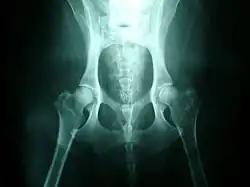

Röngenfoto van beiderzijds dysplastische heupen